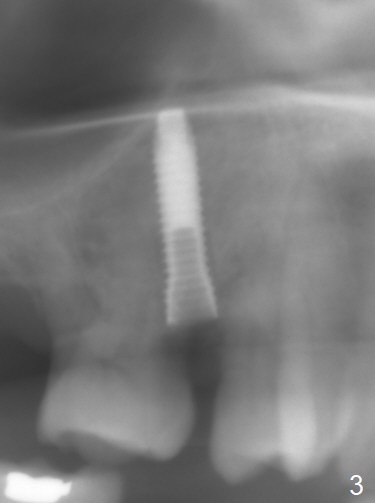

After extraction of residual root at #4 with mesiopalatal subgingival margin (Fig.1), the mesiopalatal crestal bone loss is noted. Instead of the mesial slope, the initial point of the osteotomy is at the mesial and middle (buccopalatally) of the socket bottom (Fig.2, 2'). The initial depth with 2 mm drill is 20 mm (gingival level), while the last drill (3 mm) is used for 17 mm (because of soft bone). When a 3.8x16 mm implant is placed (Fig.3,4), the distal gap of the socket is closed, suggesting that the implant moves to the least resistant area. However, it is favorable to the mesial crestal defect (Fig.4). The buccopalatal position of the abutment (4.5x4(4) mm) is a little too palatal (Fig.5, taken prior to provisional fabrication). The implant seems to have osteointegrated 6 months postop (Fig.6).